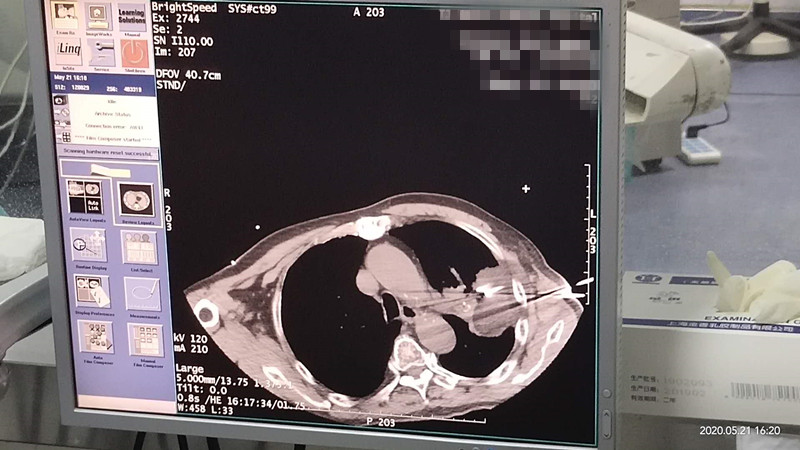

76岁肺部氩氦刀冷冻消融

发布人:美国氩氦刀技术官方网站    发布时间:2020/5/22 15:12:45